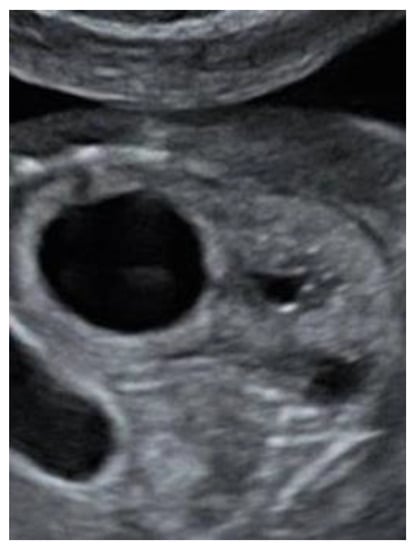

Figure 2). The lateral ventricles were not dilated. Ultrasound examination of the spine revealed a closed skin except for a minimal fistula in the sacro-coccygeal region (

Figure 3,

Figure 4 and

Figure 5). Furthermore, an abnormal gap between the second and third digit was seen on both hands as well as a syndactyly between the first and second toe. Cardiac sonography was normal at both 17- and 24-weeks GA, with a normal four-chamber view, outflow tracts, and three-vessel view. An amniocentesis was performed to rule out genetic anomalies and to measure alfa 1-fetoprotein. Additionally, a fetal MRI was carried out mainly to assess the fetal spine, as the cerebral findings all indicated the presence of an open neural tube defect. MRI analysis confirmed the hydroureteronephrosis as well as the lemon-shaped skull, Arnold–Chiari malformation 11mm below the foramen magnum, absent cerebrospinal fluid around the cerebellum, and possible mild tethering of the cord. However, MRI failed to demonstrate an open spina bifida or any skin defects. The Alfa 1-fetoprotein was elevated, further reinforcing the assumption of a classic spina bifida. QF-PCR showed no aneuploidy for chromosomes 13, 18, 21, X, or Y, but SNP array demonstrated a terminal multiplication of approximately 56 Mb of the long arm (3q23qter) of chromosome 3: arr 3q23q29(141903905-197845233)x2~4. The nature of the multiplication could not be deduced. Interphase FISH with probes in chromosomal regions 3q26 and 3q27 showed 4 copies of both chromosomal bands in approximately 50% of the interphases. Metaphase FISH proved that the 2 extra copies were located on a marker chromosome. Chromosomal examination of the parents showed no anomalies, demonstrating that the aberration occurred de novo in the fetus. Note, a genome-wide NIPT analysis on a blood sample taken at 27 weeks GA failed to detect this anomaly despite its size, indicating this to be a true fetal mosaicism of type 5 (TFM5).